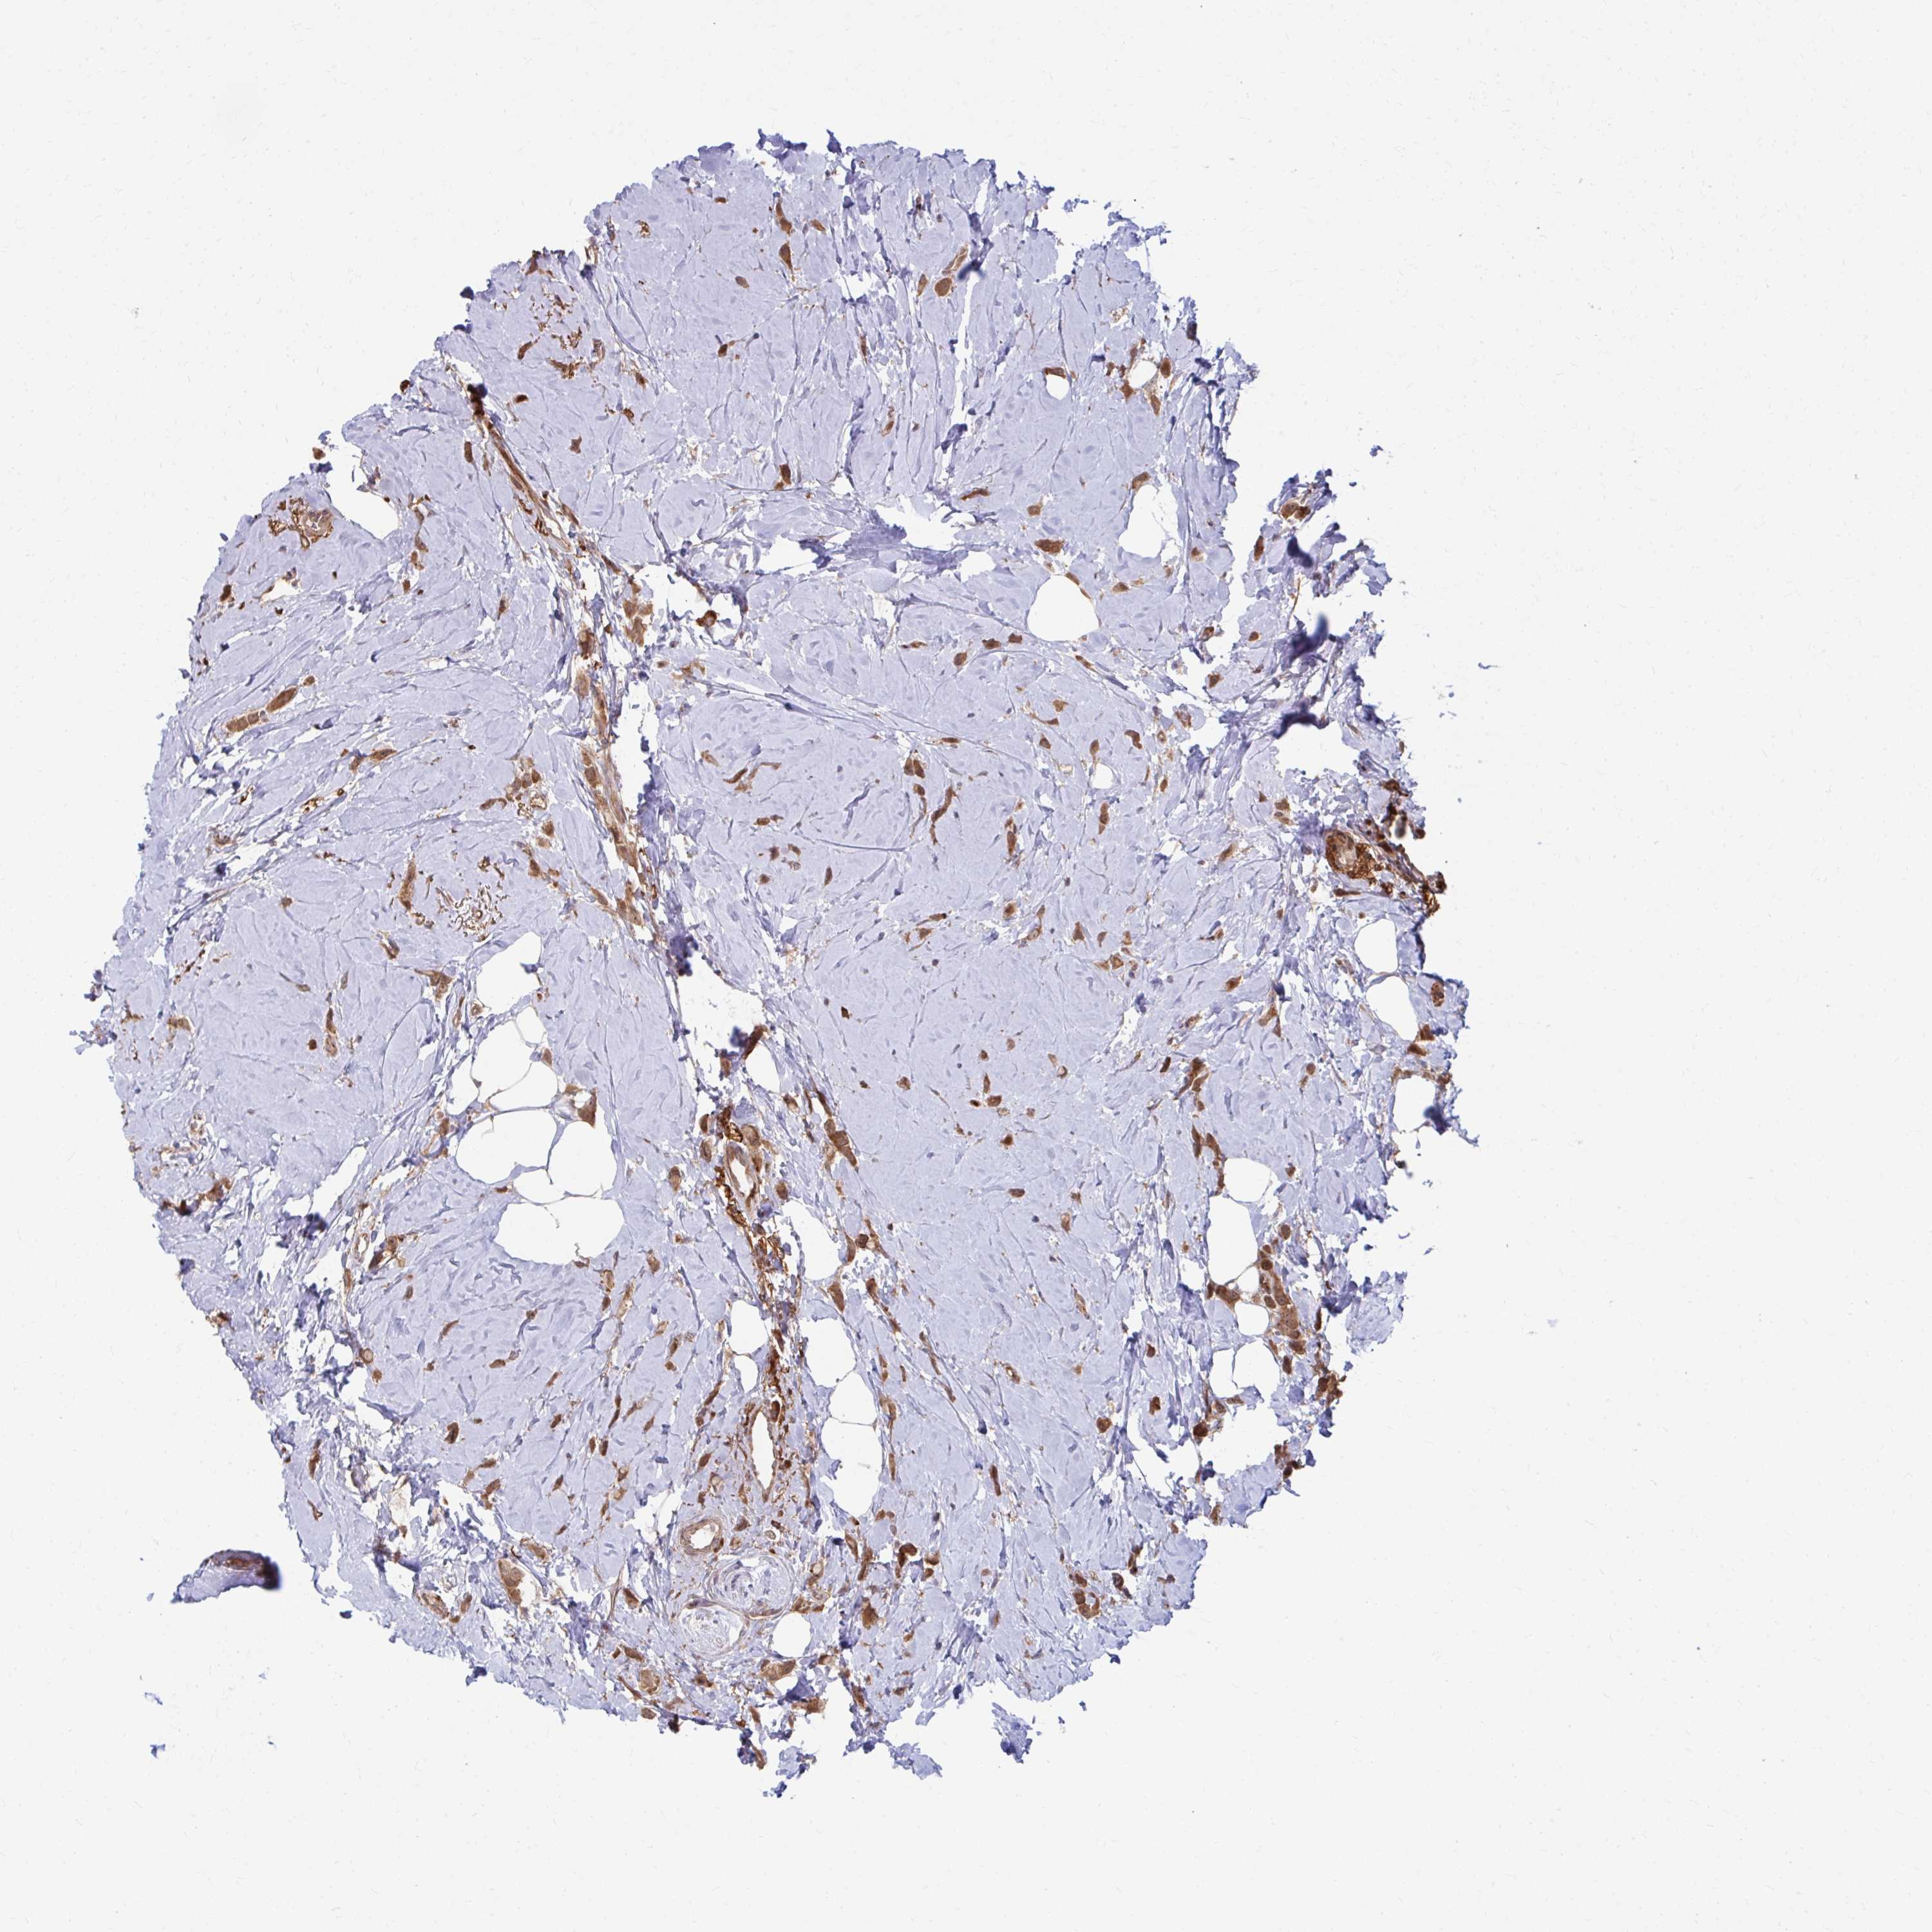

CANCER BREAST CANCER Show tissue menu

BRCA TCGA BRCA VALIDATION PROTEIN EXPRESSION